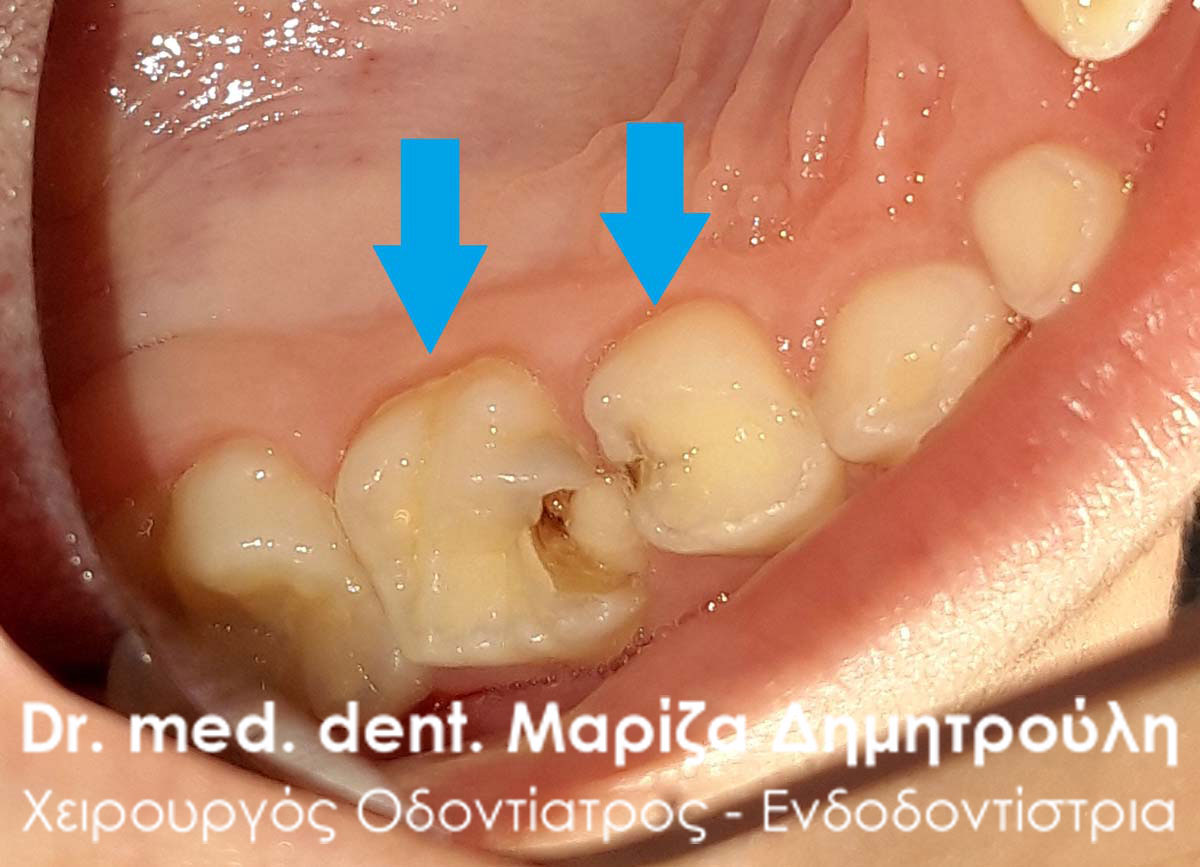

Dental fillings of primary teeth

AFTER

AFTER